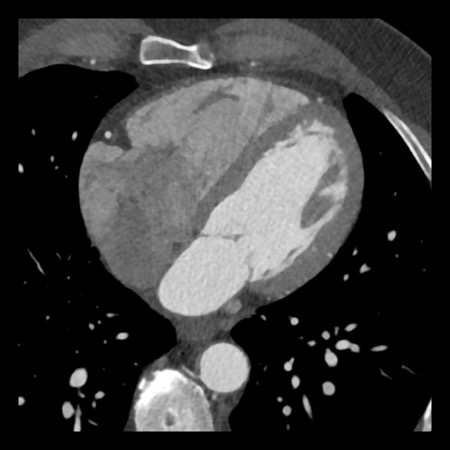

case 4 – CAD-RADS 3/P1/I+ thrombus left ventricle

First, scroll through the CTA images.

How would you describe the findings on the coronary CTA?

The findings are:

- Moderate (50-69%)

stenosis in the proximal LAD caused by a non-calcified plaque. - Variant of

sinoatrial (SA) nodal artery. The artery usually arises from the RCA as a second

branch after the conus artery, however in this case it arises from the LCX,

courses behind the aorta, anastomosing with the right atrium and with a small

branch supplies the SA-node of the heart. - Thrombus in the

apex of the left ventricle. - CTP was performed

in this patient. CTP showed a perfusion defect at stress imaging in the

territory of the LAD (I+), at rest no perfusion defect was visible.

This patient classifies as CAD-RADS 3/P1/I+, which means

this patient requires further investigation.